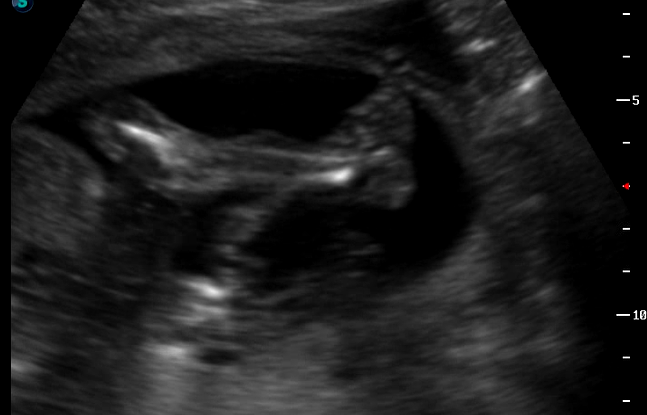

ну и несколько фото:

всё узи скрещивал ножки словно на пляже лежит)